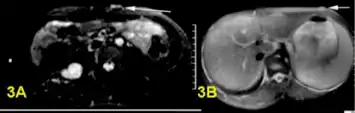

- a,b)Bright plexiform neurofibroma

- Histopathology of neurofibroma: A spindle cell lesion composed of slender fibroblast-like cells with storiform pattern and very low amount of stroma.[16]